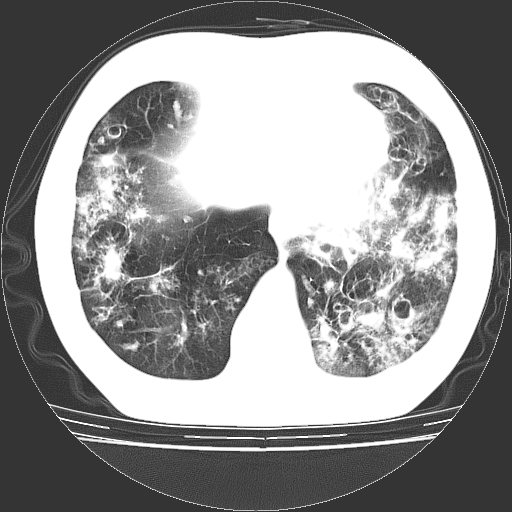

以下是引用zyx168在2006-12-4 15:30:00的发言:[br]经典!支气管肺囊肿并感染。

以下是引用dyqct在2006-12-4 17:11:00的发言:[br]典型的囊状支扩合并感染。

以下是引用liaoqiang在2006-12-4 16:12:00的发言:[br]局部肺叶内可见扩张的支气管壁,考虑为支扩。部份囊样影内有小液平和肺内散布斑片征影、小结节及纤维灶,提示支扩伴感染,且由于局部呈现有树芽征感染以结核可能性大。

以下是引用zhoucan076在2006-12-4 16:48:00的发言:[br]囊状支扩合并感染